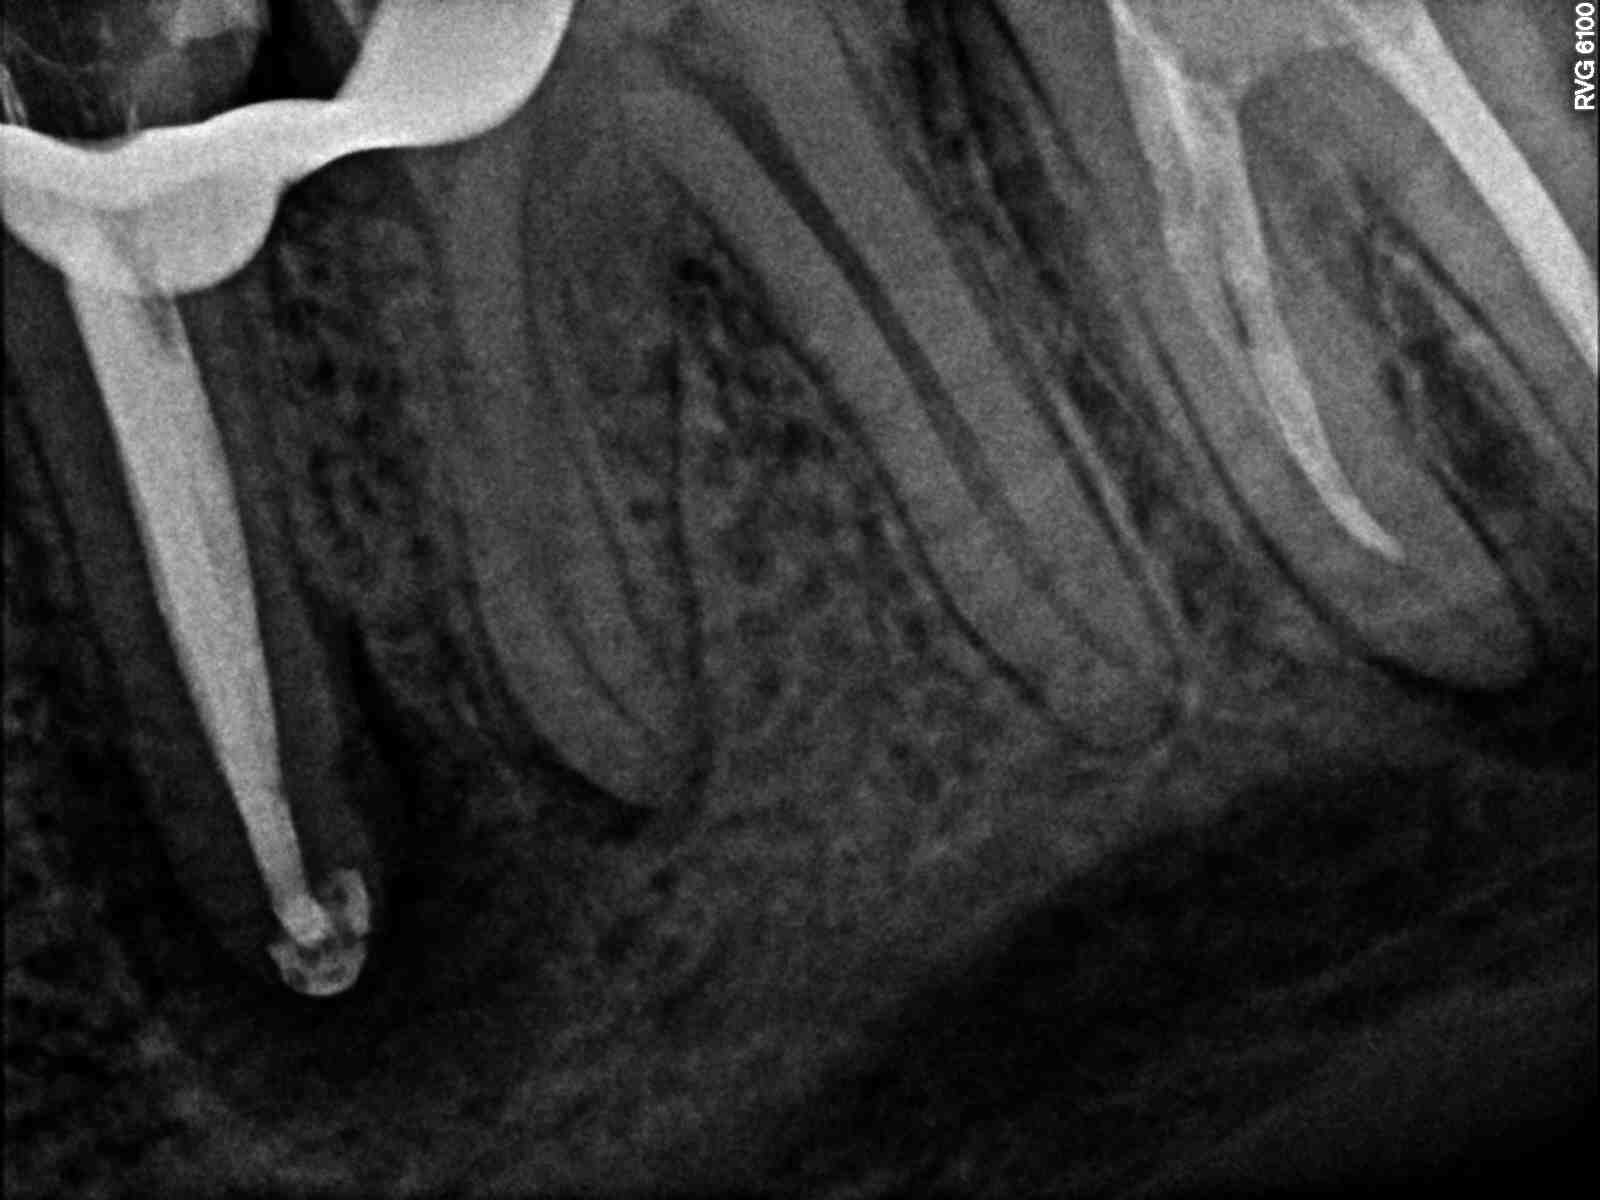

Drugi przedtrzonowiec w żuchwie uratowany. W wyniku terapii endodontycznej nastąpił całkowity zanik zmiany zapalnej w rejonie drugiego przedtrzonowca w żuchwie po lewej stronie. Leczenie kanałowe z użyciem mikroskopu była dodatkowo utrudniona ze względu na pacjenta i jego odruch refluksu. Pacjent zgłosił się do placówki NZOZ Stomatologia Bez Bólu bardzo narzekając na ból, jak określił nie do wytrzymania w żuchwie po lewej stronie. Podczas badania radiologicznego OPG i RVG stwierdzono dużą zmianę zapalną w okolicach wierzchołka korzenia drugiego przedtrzonowca w żuchwie po lewej stronie, generującą zanik kość w tym sektorze żuchwy.

Po 10 miesiącach na zdjęciu kontrolnym widać wyraźnie całkowite odbudowanie struktury kostnej okalającej korzeń zęba – drugiego przedtrzonowca w żuchwie po lewej stronie.